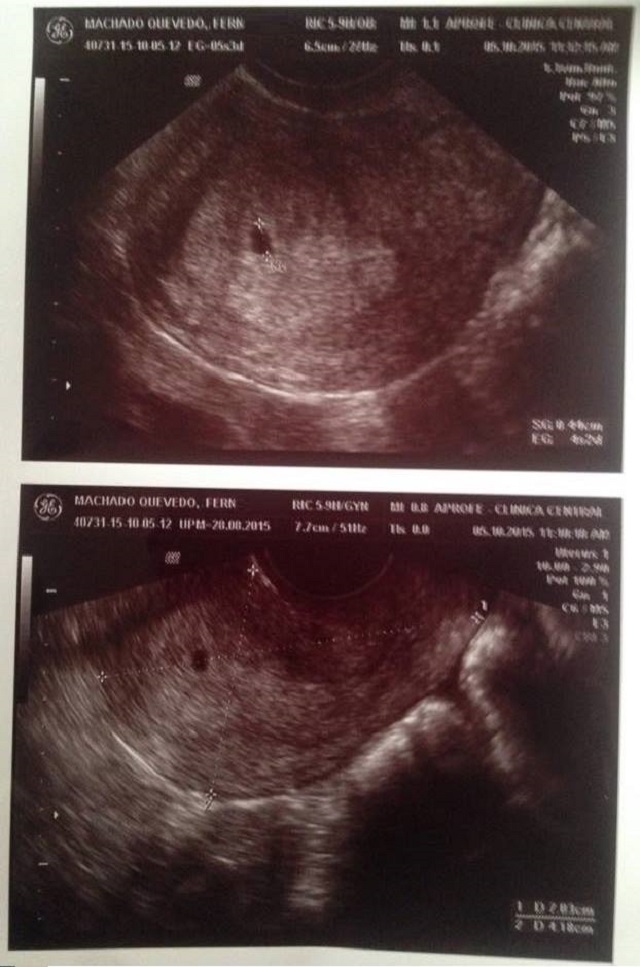

Din fericire pentru ei, familiile au fost de acord cu această schimbare de viață și i-au sprijinit. Vestea despre sarcină a fost făcută online și au împărtășit cu prietenii primele ecografii cu bebelușul și cu testul de sarcină. Cei doi au dezvăluit că au conceput copilul natural, de vreme ce niciunul dintre ei nu a renunțat încă prin operație la organele sexuale.